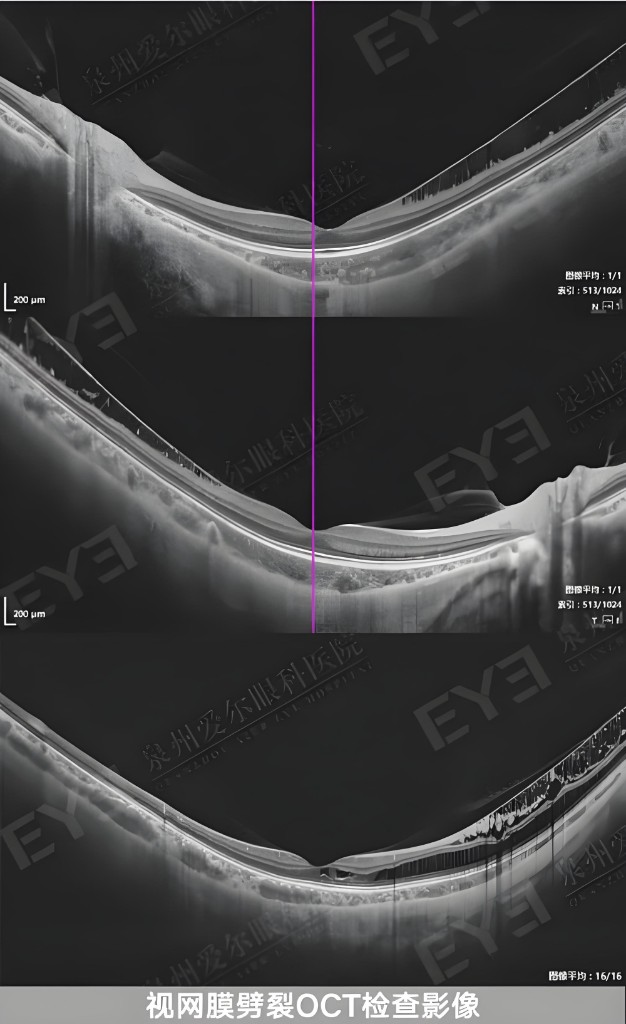

眼科 OCT 光学相干断层扫描成像仪

便携式眼科 OCT 照相机

医学影像智能分析系统(眼科影像、肠道、宫颈)

眼科 OCT 成像仪